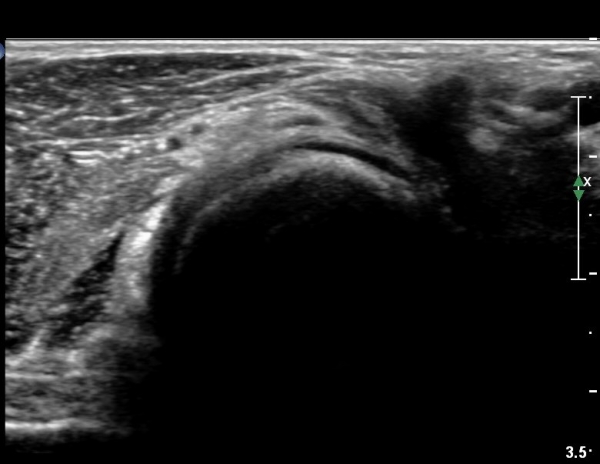

ŽÃÊÀÚ¸¦¸»´ÜÀ¸·Î  À̵¿ÇÏ´Ï ¿ä°ñ¸ñ ºÎÀ§¿¡¼­ Ä¿´Ù¶õ ³¶Á¾ÀÌ Èİñ°£ ½Å°æÀ» ¾Ð¹ÚÇÏ´Â °ÍÀÌ

°üÂûµÈ´Ù(»çÁø 4, 5)